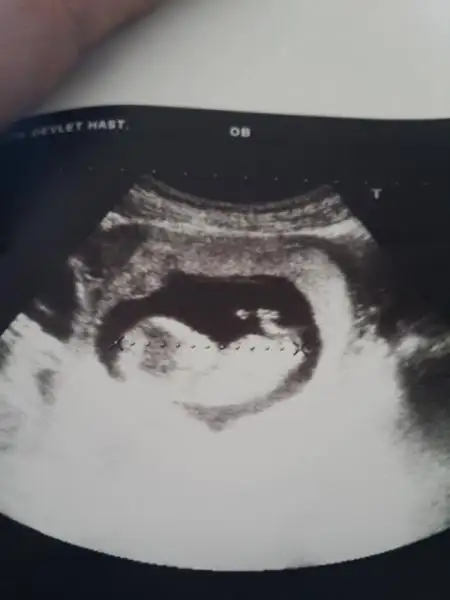

dr soylemeden siz gorun genital nub teorisi ( bebegin cinsiyeti)

Canım bu benim.oğlumun 12 haftalıkkenki ultrasonu

..nub.a bak kızım diye bağırıyor, Dr.da kız demişti zaten bana ama erkek çıktı benşm bebiş yanılttı bizi en son ultrasonda pipisini gösterdi Dr.umuz..bazen erkek nubları erken haftalarda kıza benzer açıklaması yaptı bize dr..gerçi değiştirdim Dr.umu ama sizinle paylaşayım dedim:)